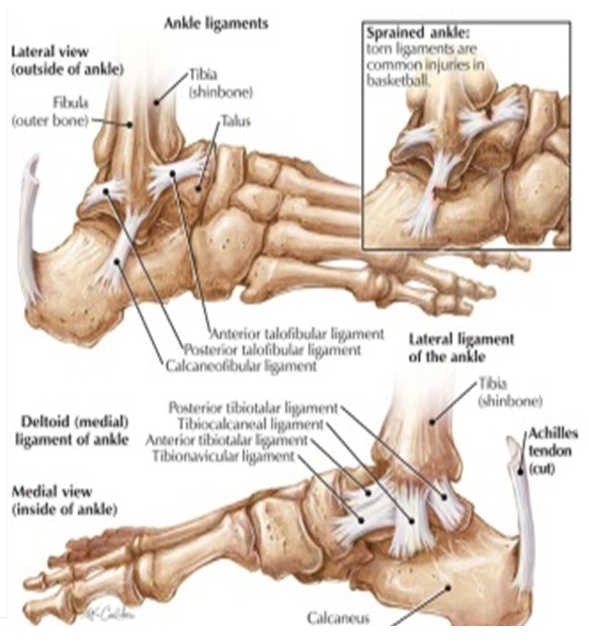

Foot Muscles Mri Anatomy : MRI Ankle Anatomy | Ankle Anatomy, Anatomy

bakeca-donnacerca-uomo-bologna.blogspot.com

bakeca-donnacerca-uomo-bologna.blogspot.com

mri ligament deltoid anatomy foot injury tear muscle coronal tendon diagnosis abnormal injuries radiology muscles biomechanics ray arthritis severe lead

Foot Muscles Mri Anatomy : MRI Ankle Anatomy | Ankle Anatomy, Anatomy

bakeca-donnacerca-uomo-bologna.blogspot.com

bakeca-donnacerca-uomo-bologna.blogspot.com

mri plantar axial nerve lateral t1 ankle medial weighted brevis flexor entrapment mpn trescot md digitorum calf intrinsic ligament fasciitis